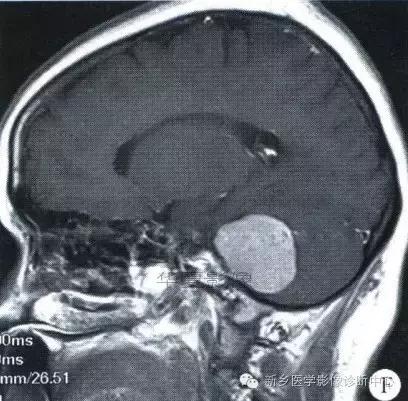

中枢神经系统内原发性黑色素瘤少见, 因脑和脊髓的软脑( 脊) 膜及蛛网膜上含有黑色素细胞, 黑色素可发生于软脑( 脊) 膜的任何部位,故其发生部位常位于脑( 脊髓) 表面, 沿软脑膜生长; 而继发性黑色素瘤同一般转移性肿瘤, 常位于灰白质交界区。

影像表现:常表现为短 T1 高信号, 短T2WI 低信号,又因为黑色素瘤是富血管性肿瘤, 增强扫描常表现为明显强化。

★但少数肿瘤也不具备上述典型信号特征,主要原因是肿瘤内黑色素量多少影响。只有当黑色素瘤中黑色素细胞超过一定含量( ﹥ 10% ) 时, 才会出现黑色素瘤的典型MRI表现; 不典型的黑色素瘤因其黑色素含量较少,不足以缩短T1、T2弛豫时间,而表现为长T1低信号、长T2高信号。

依据黑色素瘤的不同 MRI 影像表现将其分为 4 种类型: ( 1) 黑色素型。该黑色素瘤因含有丰富的黑色素颗粒, MRI表现较典型,即短 T1 高信号,短 T2 低信号。( 2) 无黑色素型。因该类黑色素瘤不含黑色素颗粒或含量较低,MRI 表现为长 T1 低信号,长 T2 高信号; ( 3) 混合型。黑色素型和非黑色素型两者的混合; ( 4) 出血型。表现为血肿不同时期的信号特征, 该黑色素瘤 MRI增强扫描表现为不均匀环状或弥漫性强化